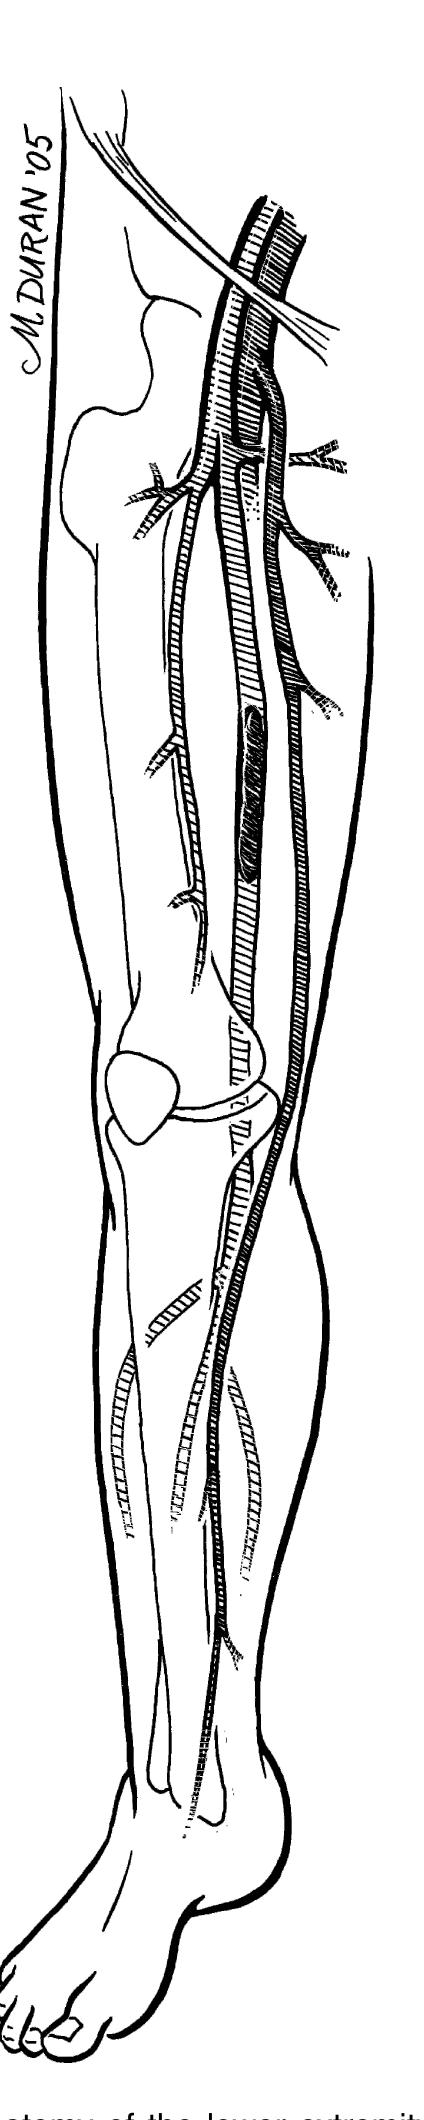

The paper discusses the surgical anatomy and techniques associated with various procedures, with particular emphasis on the anatomy of the scalp, including its vascular, lymphatic, and nerve supplies. It presents detailed insights into the blood supply of the scalp, highlighting the important arterial branches and their anastomoses, as well as the implications for surgical procedures. Additionally, the paper outlines techniques for surgical interventions, positioning, and considerations necessary for effective outcomes.

- The nerve may pass anterior or posterior to the artery, or between its branches (Fig. 2.16 ).

- The external iliac artery becomes the common femoral artery as it emanates from a point under the middle of the inguinal ligament.